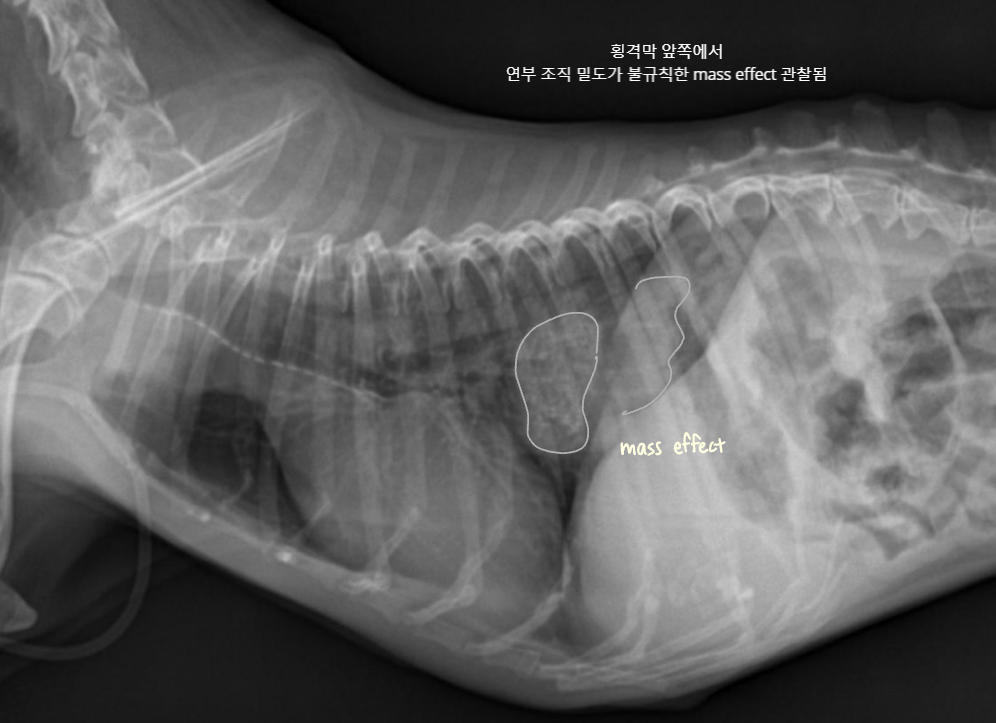

- Mass : ์๋ฆฌ๋ฅผ ์ฐจ์งํจ โ ์ฅ์ ๋ฐ์ด๋. & ์ข ์์ด ์ปค์ง๋ฉด์ ์ถํ์ ์ ๋ฐ.

โ ๊ณจ๋ฐ๊ฐ ๋ด์์ ์๋ mass

- 4๊ฐ์์งธ ์ฌํ ๋ณ๋น + ์์๋ถ์ง, ์ฒด์ค ๊ฐ์, ๊ฐํ์ ๊ตฌํ ๋ก ๋ด์.

- Mass๊ฐ ๊ณจ๋ฐ๊ฐ ์์์ ์๋ผ๋ฉด ๊ฒฐ์ฅ๊ณผ ์๋๋ฅผ ๋ฐ์ด๋ด๊ณ , ์ ์ฑ ๋ณ๋น๋ฅผ ์ ๋ฐํจ.

- Leiomyoma๋ก ์ง๋จ๋จ.